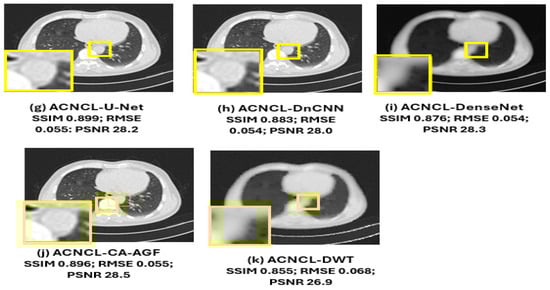

| ACNCL-U-Net | 0.899± 0.025 | 0.056 ± 0.005 | 28.3 ± 0.9 |

| ACNCL-DnCNN | 0.883 ± 0.027 | 0.061 ± 0.005 | 28.0 ± 0.5 |

| ACNCL-DenseNet | 0.876 ± 0.028 | 0.063 ± 0.005 | 28.2 ± 0.5 |

| ACNCL-CA-AGF | 0.896 ± 0.029 | 0.057 ± 0.006 | 28.5 ± 0.9 |

| ACNCL-DWT | 0.855 ± 0.030 | 0.068 ± 0.006 | 26.9 ± 0.5 |